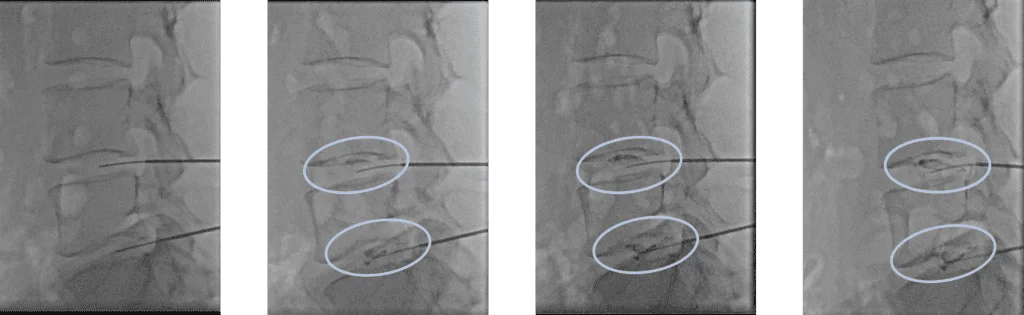

Проведена селлгель-терапия на 2 межпозвоночных дисках.

Под визуализационным контролем в диски позвоночника введен гелевый препарат, способствующий восстановлению функциональности поврежденного межпозвоночного диска.

Время лечения – около 25 минут.